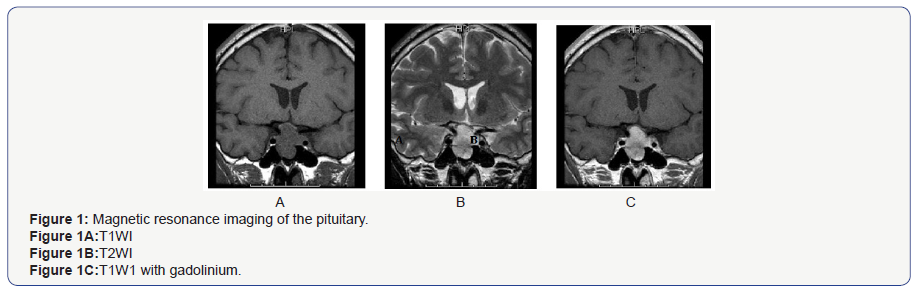

The TRH loading test indicated a poor response of TSH and PRL. This result suggested the presence of a TSH-secreting pituitary tumor because TSH secretion from a TSH-secreting pituitary tumor does not usually increase much in response to TRH [7]. In the CRH loading test, ACTH showed a poor response, but normal cortisol response. In the LH-RH loading test, FSH showed a normal response, but LH showed a poor response. In the GHRP-2 loading test, GH showed a normal response. While fasting blood glucose (96 mg/dL) and HbA1c (5.5%) were within the normal range, the IRI level (11.4 μU/mL) was slightly high. The 75-g OGTT showed 172 mg/dL of blood sugar level at 120 min, corresponding to IGT type. The insulin response was enhanced considering that he was not obese (BMI 22.2 kg/m2) (Table 1D). Magnetic resonance imaging of the pituitary showed a macroadenoma (31.4×18.3 mm), which was a low signal in T1WI (Figure 1A) and a low-high signal in T2WI (Figure 1B). There was relatively uniform enhancement by a contrast agent, gadolinium, in T1W1 (Figure 1C). Progression of the pituitary tumor to the spheroidal sinus and the left cavernous sinus, and compression to the upper part of both sides of the optic nerve and the optic chiasm were suspected. However, Goldman’s test, which is used to examine the visual field, showed no abnormalities. Thyroid echography demonstrated a diffuse swelling of the thyroid gland with a small amount of increased blood flow in the total gland. We did not observe a thyroid tumor or lymph node swelling (data not shown). Based on these findings, the patient was highly suspected to have thyrotoxicosis by a TSH-secreting pituitary tumor.